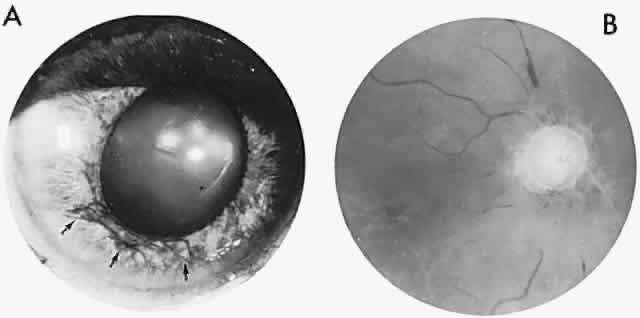

In contrast to transient symptoms and signs of retinal microembolic episodes, a condition of chronic ocular hypoxia (ocular ischemic syndrome) occurs less frequently, resulting from diffuse vascular occlusive disease of the aortic arch or common carotid artery. Acute or chronic occlusion with insufficient collateralization produces an ischemic pseudo-inflammatory uveitis, which variably includes an injected painful globe, corneal edema, aqueous flare and cells, a mid-dilated fixed pupil, rubeosis and iris atrophy, rapidly advancing cataract, either hypotony or elevated intraocular pressure (“neovascular glaucoma”), retinal microaneurysms and new vessel formation, posterior pole and mid-peripheral blot hemorrhages, macular edema, venous dilation and “sausaging,” cytoid infarcts (cotton-wool spots) of the nerve fiber layer, and arterial occlusions (Fig. 7; see Table 4). The hypoxemic fundus changes constitute a picture of venous stasis (low-pressure) retinopathy, perhaps the commonest ocular sign of chronic carotid obstruction.

Fig. 7. Ocular hypoxia with subacute carotid occlusion. The patient complained of a painful red eye. A. Anterior segment shows an irregular, fixed pupil and iris rubeosis (arrows). B. Fundus demonstrates combined retinochoroidal infarction with acute excavation of the optic disc. Arteriography revealed right internal carotid occlusion.

Ischemic photoreceptor metabolism accounts for subjective afterimages following exposure to bright light, including a positive photostress test60 (see Volume 2, Chapter 2). Low retinal arterial pressure may be detected by observing pulsation or collapse of the disc arterioles with even slight fingertip pressure exerted on the globe. Such borderline perfusion associated with carotid stenosis and retinopathy may be heralded by postprandial visual loss.61 In the situation of chronic, subacute, or rapidly progressive ischemic oculopathy, giant cell arteritis must be considered in the differential diagnosis, and chronic venous obstruction or diabetic retinopathy may produce similar fundus appearance.